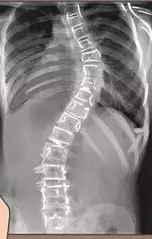

布骨医学科普:脊柱侧弯干预和不干预的差别竟然这么大!

发现侧弯以后,积极干预还是继续观察?不同的医生给出不同的答案。有的医生擅长手术,对保守治疗并没有深入的研究,有的医生虽然不做手术,但他(她)可能对侧弯的发展有很多经验。.....

脊柱侧弯|脊柱侧弯危害大,千万不要放任它!

1.什么是脊柱侧弯?脊柱前凸、脊柱后凸、脊柱侧弯。2.脊柱侧弯有哪些危害?影响脊柱外形和功能;影响生理健康;影响心肺功能;影响胃肠系统。3.脊柱侧弯如何判断?根据脊突线判断;根据形态改变判断;根据影像学证据判断。4.脊柱侧弯如何处理? 非结构性脊柱侧凸;结构性脊柱侧凸。5.躯干肌力训练方案:膝跪位腹.....